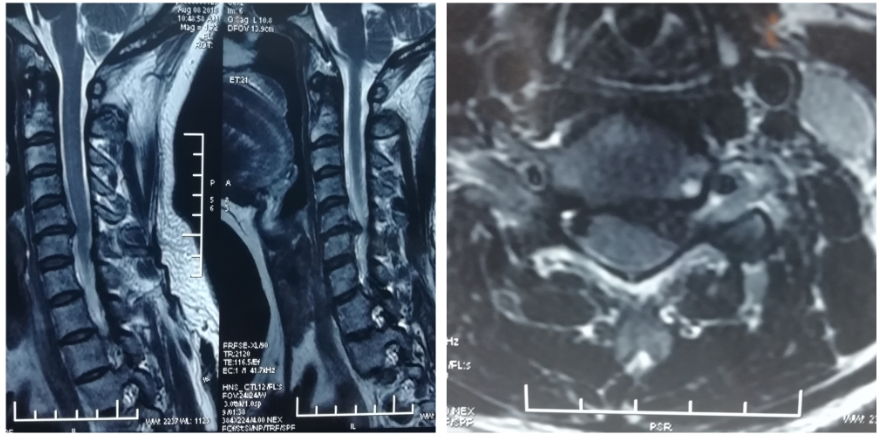

颈椎病是指颈椎椎间盘退行性改变及其继发的相邻结构病理改变累及周围组织结构(神经、血管等)并出现与影像学改变相应的临床表现的疾病。

1. 麻醉成功后定位,置入通道

2. 镜下操作

3. 摘除髓核后

4. 术后患者症状即刻缓解